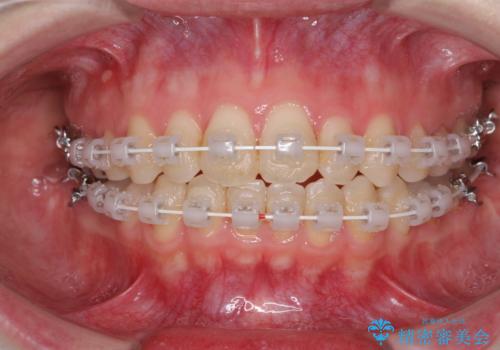

- 矯正装置

- 審美装置

治療途中で出産されたこともあり、当初予定よりも終了までに期間がかかってしまいました。

舌を前方に突出する癖があったため、上下前歯がなかなか接触しなかったことも治療期間が伸びた要因です。